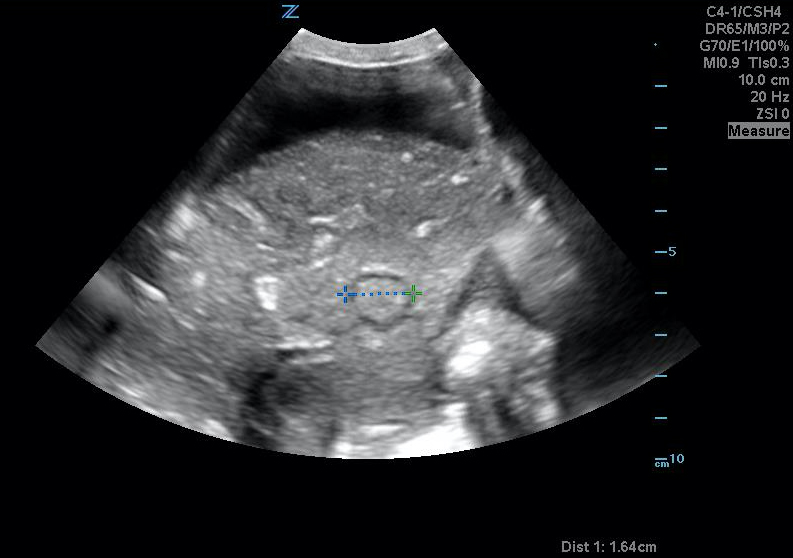

- After scanning the entire uterine cavity systematically (mowing the lawn), find and measure the single deepest pocket of anechoic amniotic fluid perpendicular to the bed with no fetal parts present. The probe marker should be pointing to the patient’s head.

- Normal ranges from 2cm – 8cm

Figure 37. A normal greatest vertical pocket of amniotic fluid. Note the calipers measuring the deepest pocket of amniotic fluid not containing any fetal parts.